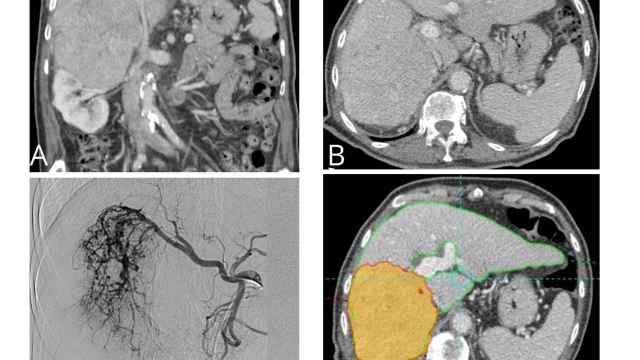

Cáncer de hígado y conducto biliar

Un reconocimiento a su trabajo, centrado en comprender el doble comportamiento de la proteína TGF-beta en el colangiocarcinoma, un cáncer de los conductos biliares que representa en torno al 3% de las neoplasias digestivas y que se caracteriza por su diagnóstico tardío, corta supervivencia mediana y alta tasa de recurrencia tras la cirugía.